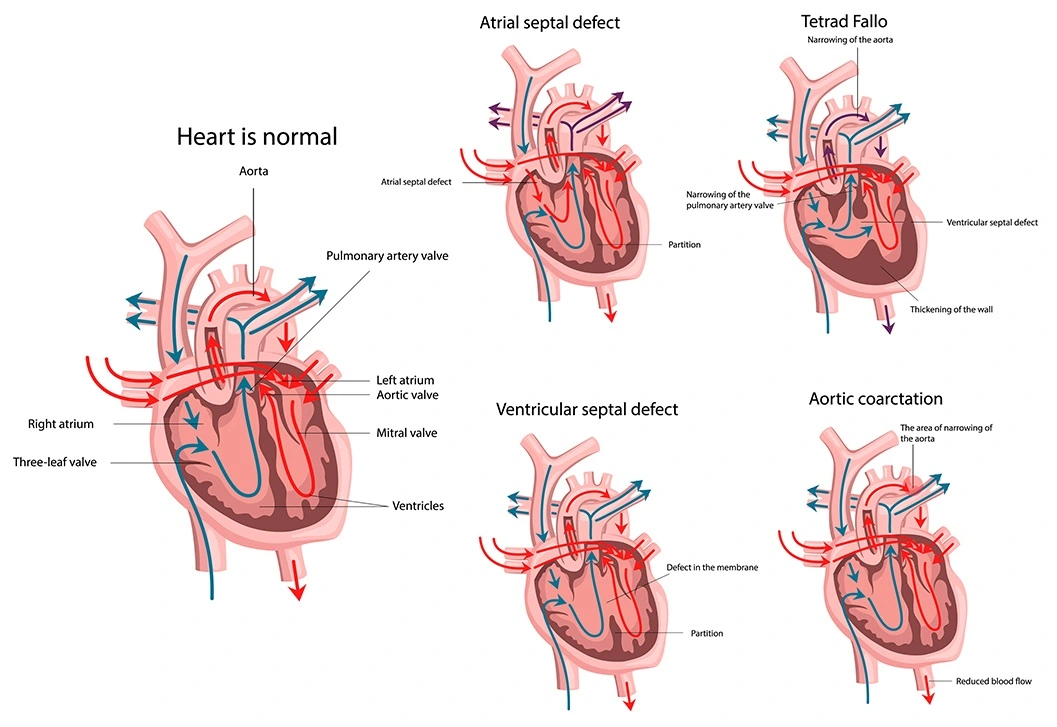

Overview

Package includes:

Days in hospital : 10 to 11 Days (For patient and one attendant)

Days in hotel : 14 Days (For patient and one attendant)

Room type in hospital : Shared

Room type in hotel : Private

Hotel category: Standard

Value added benefits of the TOF treatment:

Overview

Package includes:

Days in hospital : 10 to 11 Days (For patient and one attendant)

Days in hotel : 14 Days (For patient and one attendant)

Room type in hospital : Shared

Room type in hotel : Private

Hotel category: Standard

Value added benefits of the VSD Closure:

Overview

Package includes:

Days in hospital : 10 to 11 Days (For patient and one attendant)

Days in hotel : 14 Days (For patient and one attendant)

Room type in hospital : Shared

Room type in hotel : Private

Hotel category: Standard

Value added benefits of the AVSD Closure:

Overview

Package includes:

Days in hospital : 10 to 11 Days (For patient and one attendant)

Days in hotel : 14 Days (For patient and one attendant)

Room type in hospital : Shared

Room type in hotel : Private

Hotel category: Standard

Value added benefits of the ASD Closure: